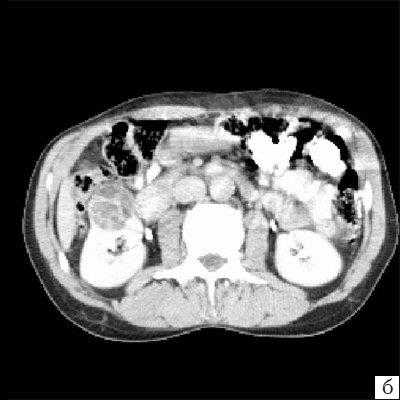

Достоверность комьютерной томографии (КТ) в диагностике мультилокулярной кистозной нефромы, по данным разных авторов, составляет от 95 до 98%. При КТ определяется негомогенное многокамерное образование округлой или неправильно-округлой формы, возможно с капсулой, плотность образования неоднородная, пониженная относительно паренхимы, в полости образования определяется большое количество перегородок (рис. 3). Если при КТ с контрастированием происходит накопление контрастного вещества, это может быть признаком предполагаемой малигнизации [11, 13, 19].

а) До внутривенного контрастирования определяется негомогенное образование неправильной округлой формы с капсулой и едва заметными перегородками, плотность ниже, чем плотность паренхимы почки.

б) После контрастирования отчетливо выявляются плотная стенка и множество перегородок.

Компьютерная томография. В нижнем полюсе правой почки определяется неоднородное образование, с четкими неровными контурами, округлой формы, в диаметре до 30 мм, неоднородно пониженной плотности от +15 до +18 HU по шкале Хаунсвильда. После внутривенного контрастирования образование не изменят свою форму, размеры и плотность. В полости образования выявляются множественные перегородки, накапливающие контрастное вещество, единичный кальцинат.

Заключение: Сложное кистозное образование нижнего полюса правой почки, больше данных о мультилокулярной кистозной нефроме (рис. 5).

а) До внутривенного контрастирования определяется негомогенное образование округлой формы, с единичным кальцинатом, плотность ниже, чем плотность паренхимы почки.

б) После контрастирования (паренхиматозная фаза) отчетливо выявляются плотная стенка и множество перегородок.